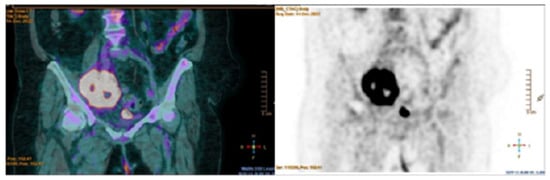

- The fundamental role of multimodality imaging (TTE + TEE, brain MRI, 18F-FDG/PET–CT scan) for NBTE diagnosis;

- Papakonstantinou, K.; Rorris, F.P.; Stanitsa, N.; Kokotsakis, J. PET-scan in diagnosis of non-bacterial thrombotic endocarditis: A case report. Egypt. Heart J. 2024, 76, 21. [Google Scholar] [CrossRef] [PubMed]